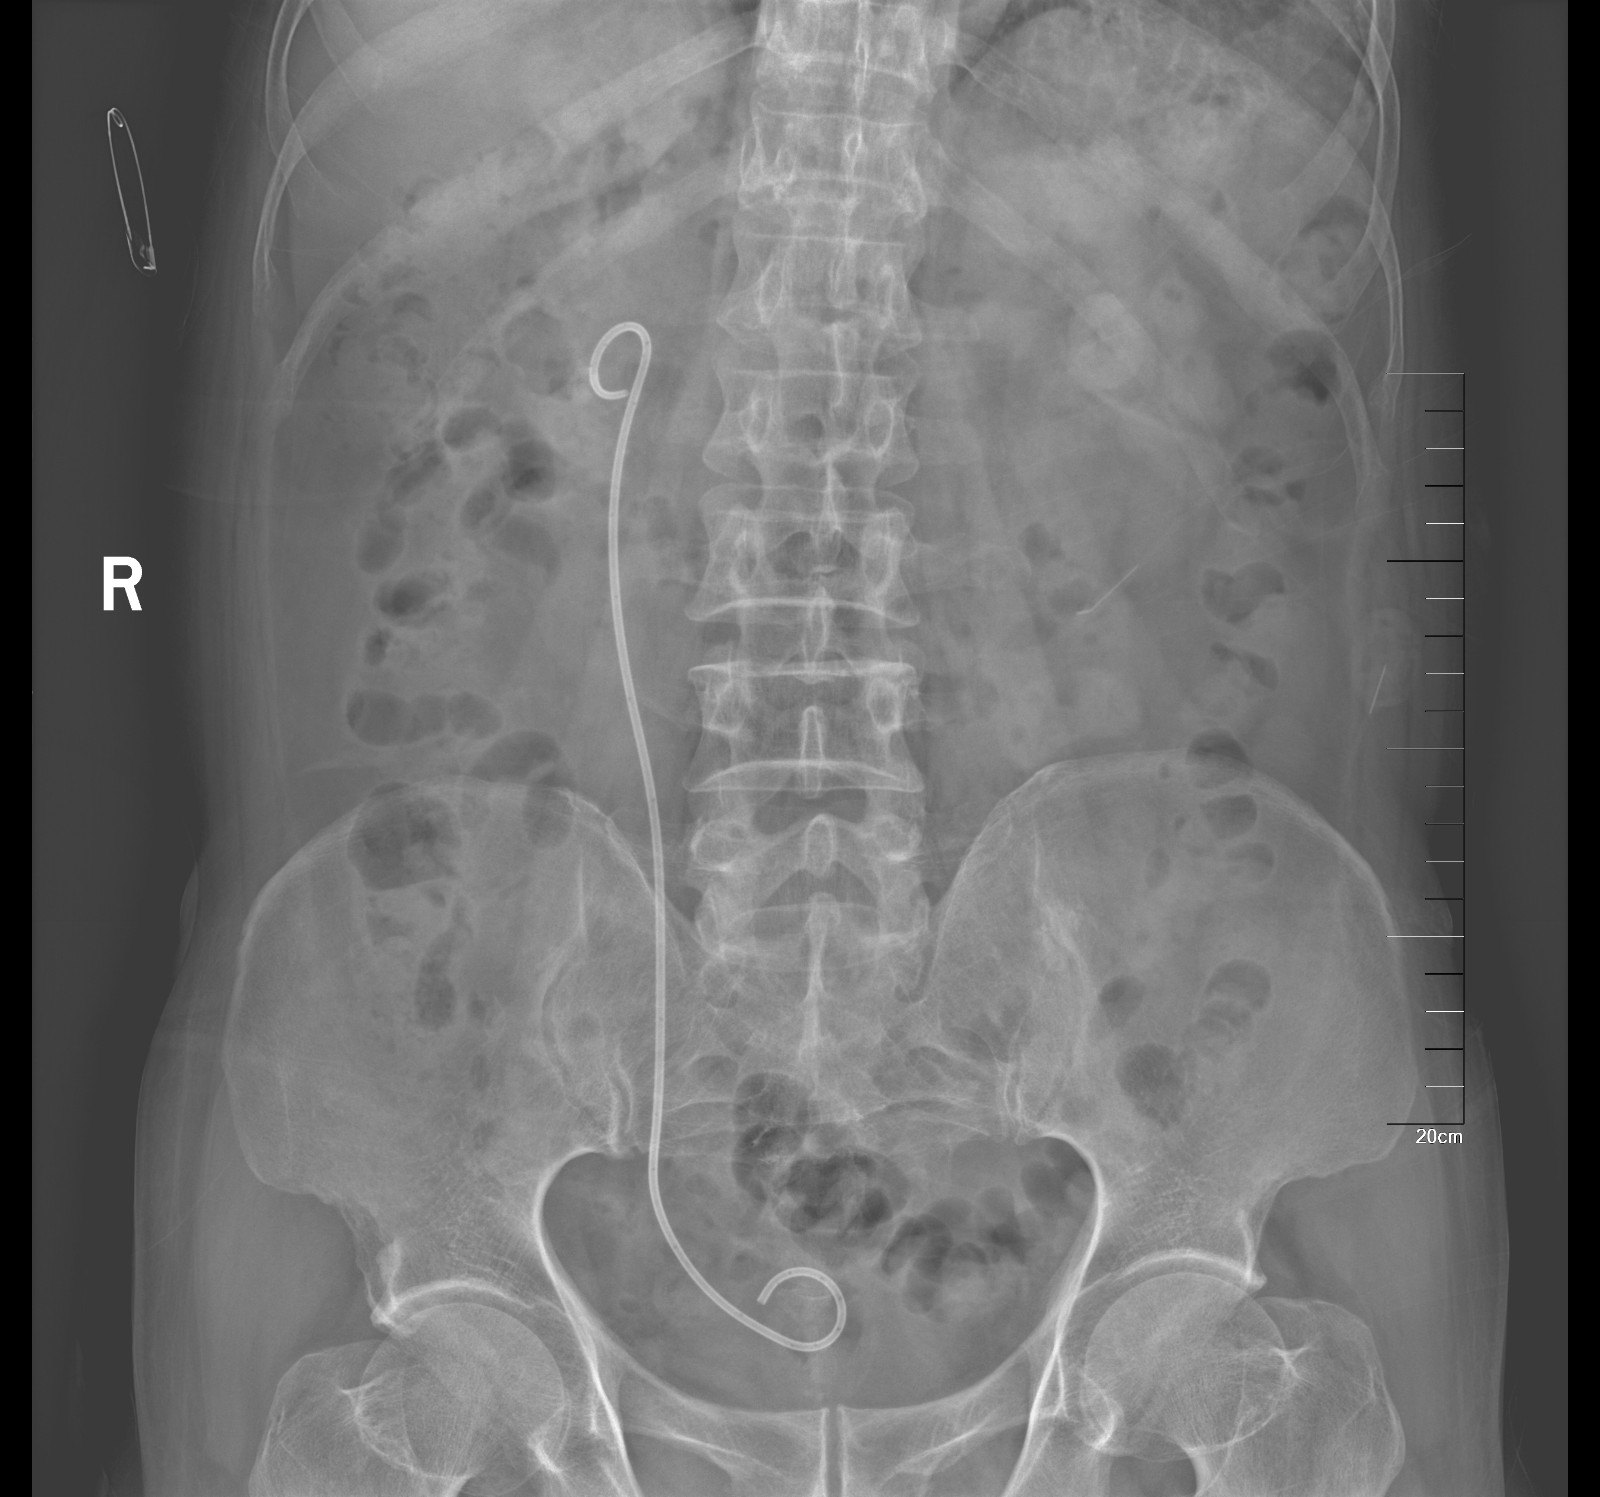

术后KUB见双肾造瘘管,及双侧内支架管固定妥善

双侧输尿管切开取石术+双侧输尿管裁剪成型术,术中见上段输尿管因梗阻扩张似肠管,与周围脏器黏连明显,输尿管切开见结石周围包裹息肉,取石钳完整取出结石,双侧输尿管裁剪成型并留置内支架支撑。

入院后行双侧经皮肾穿刺造瘘术,保护肾功能,十天后Cr下降至236umol/L,顺行造影检查发现双侧输尿管迂曲扩张明显,双侧输尿管结石完全梗阻,造影剂无法进入膀胱。